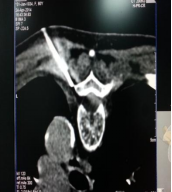

1. Spinal nerve electrostimulation therapy

Spinal nerve electrostimulation therapy is to appropriately stimulate the nerve area producing pain by small electric pulse, feedback adjust nerve conduction substances, and produce tolerable numbness to replace pain, so as to play the role of relieving pain. It is effective for treating herpes zoster, and has the following advantages: